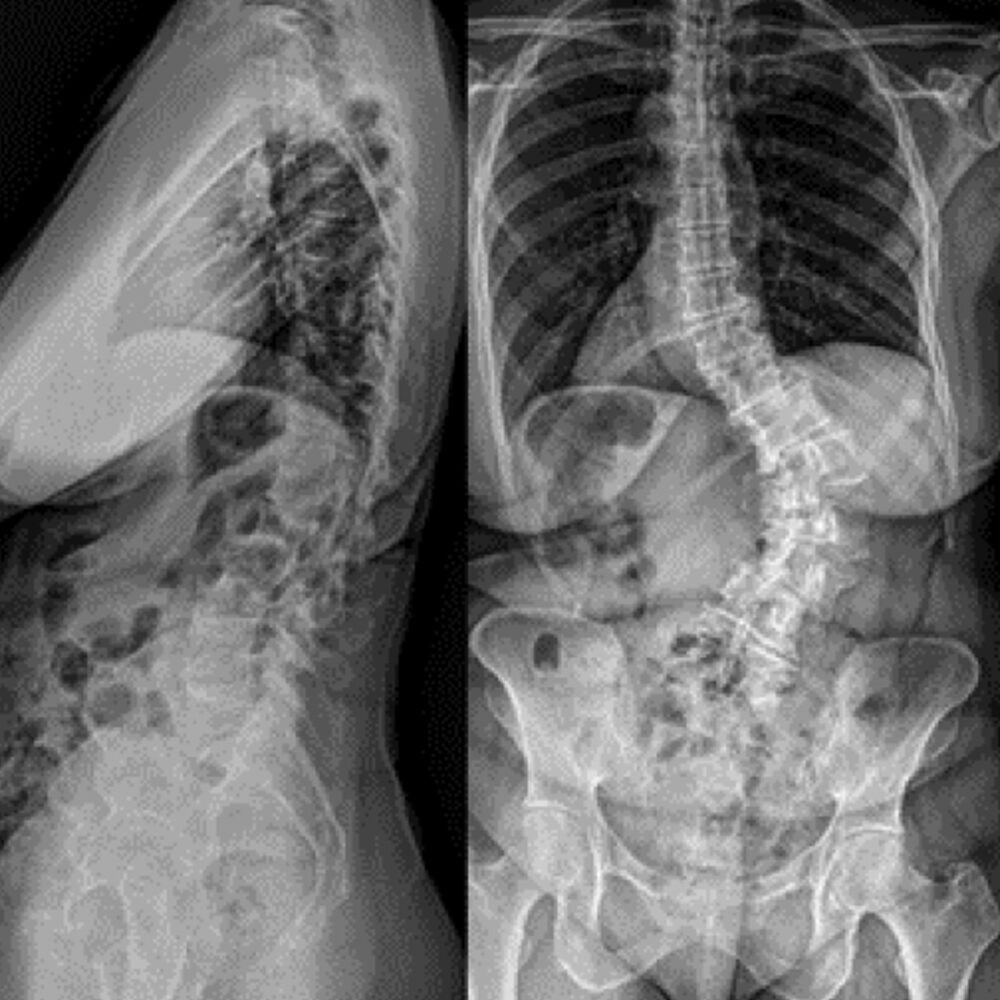

Adult Scoliosis

Patient History:

- Idiopathic adult scoliosis with degenerative changes

- Disabling back and leg pain

- Spondylolisthesis

Surgical Treatment:

- ALIF L5-S1

- T10-pelvis posterior fusion with bilateral placement of S2AI screws and S1AI Bedrock® trajectory iFuse 3D™ implants for SI joint stabilization

Post-op:1,2

- No complaints of back/leg pain at 2-year follow-up

- Back to full-time work as a high-level executive and public speaker